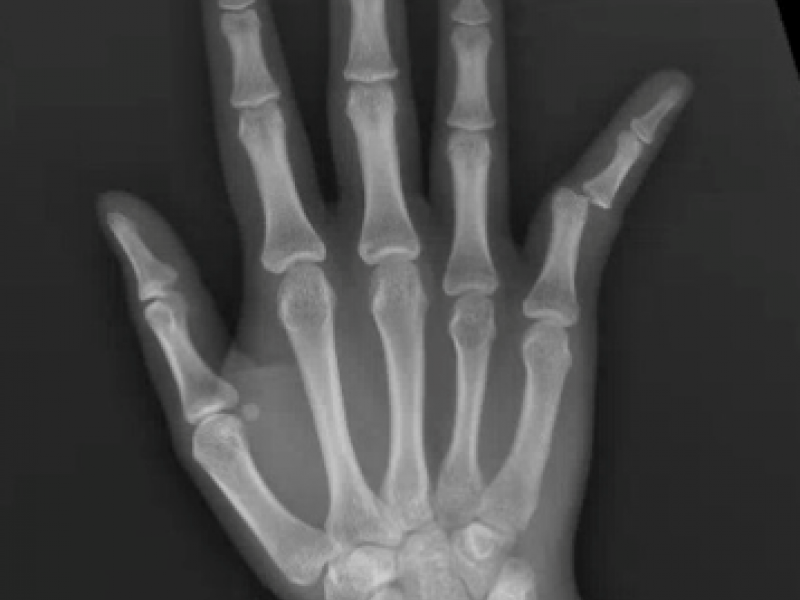

What's the Diagnosis? By Dr. Lynn Manganiello

A 13 year old female presents with right 5th digit pain and